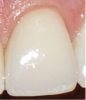

Translucency on the incisal edge of a tooth and intact gingival margin may indicate moderate erosion. In severe cases, the morphology of the tooth becomes significantly altered, which may lead to dentin and/or pulp exposure (Figure 4). The white translucent enamel becomes worn from the surface, leaving yellow dentin and reddish pulp. Worn incisal edges of teeth can be prone to further weakening and fractures. Exposed dentin can cause hypersensitivity to cold, hot, and tactile stimuli.21 If untreated, an exposed pulp may be susceptible to infection and necrosis.

Fig 4. Facial erosion with aggressive abrasion of maxillary anterior teeth. Note pulp exposure on facial surface of canine.

Figure 4